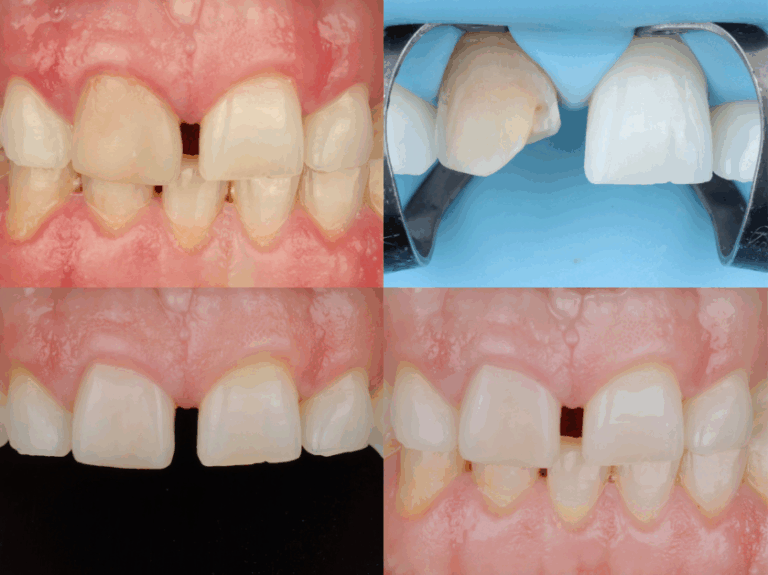

Šis kursas parengtas remiantis kasdiene klinikine patirtimi, dirbant su endodontiškai gydytais ir estetiškai komplikuotais dantimis, kai gydymo sprendimus riboja biologiniai, klinikiniai ar finansiniai veiksniai. Kurso metu nagrinėjamas konservatyvus požiūris į gydymo planavimą ir tiesioginių restauracijų taikymą, siekiant prognozuojamų ir ilgalaikių rezultatų. Kurso metu dalinamasi klinikine sprendimų logika, leidžiančia racionaliai parinkti gydymo taktiką, optimaliai išnaudoti kompozitinių restauracijų galimybes ir sumažinti nereikalingą invazyvumą, išlaikant estetinį ir funkcinį stabilumą. Kursas skirtas gydytojams odontologams, siekiantiems gilinti supratimą apie konservatyvų restauracinį gydymą, stiprinti pasitikėjimą klinikiniais sprendimais ir taikyti praktiškai pagrįstus metodus kasdienėje klinikinėje veikloje.

• Negyvo danties spalvos pokyčiai. Endodontiškai gydyto danties estetiniai iššūkiai ir spalvos pokyčių mechanizmai.

• Kodėl laminatės tamsiems dantims dažnai tampa invazinės. Gydymo strategijų palyginimas: balinimas, laminatės, vainikėlis ar tiesioginė kompozitinė restauracija.

• Substrato neutralizavimo ir spalvos kontrolės strategijos. Substrato įvertinimas ir restauracijos plano sudarymas.

• Opakerių taikymas ir maskavimo strategijos.

• Dentino ir emalio sluoksniavimo seka tamsiam fonui.

• Estetinės formos kūrimas.

• Šlifavimo ir poliravimo gairės, kai dantis stipriai diskoloruotas.